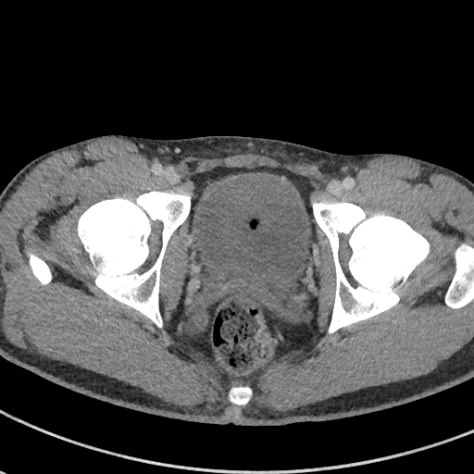

Fig. 3 visualizes sample abdominal CT images with varying quality levels from the test set. The predicted IQA scores show strong agreement with the reference scores across different noise and artifact intensities, which indicates the robustness of CAP-IQA in accurately quantifying CT image quality. The kernel density plot in Fig. 4 illustrates how prediction residuals are distributed across different IQA score groups. All curves are centered near zero, indicating balanced predictions without systematic bias toward any specific quality range. Moreover, the box plot presents the distribution of absolute prediction errors across different IQA score groups. The median errors remain low and consistent, showing that CAP-IQA performs reliably across all quality levels, with minimal variations and stability in predictions. Consistent with this interpretation, our pairwise testing using the Kruskal-Wallis H-test further confirms that there is no significant difference in performance for different IQA score groups (p-value 0.38).

4.8 Real Clinical Evaluation

We also evaluated the proposed CAP-IQA model on an in-house dataset. Fig. 8 displays sample images from the dataset. We retrospectively collected real clinical CT images from the University of Kentucky Medical Center with approval from the Institutional Review Board. A total of 91,514 image slices from 336 pediatric patients aged 2-12 years were used for testing the generalizability of CAP-IQA. Since these images have already been used for clinical diagnosis, they are expected to be of high quality (>3, as per the IQA scoring criteria in Table 1). Slice-wise IQA scores predicted by the model were averaged to obtain the overall score for each of the CT scans. The average IQA score across the 336 pediatric scans is 3.8582, with a correlation of variation of 2.1447. As seen in Fig. 9, the predicted scores are tightly grouped around the mean, with scores above the diagnostic-quality threshold of 3. The relatively high predicted scores align with expert radiologists’ assessments, indicating that the scans retain good diagnostic quality. Overall, the results demonstrate that CAP-IQA performs reliably in real-world clinical settings, and the model consistently and accurately assesses quality across diverse patient data.

![]() |

| 3.95 | 3.71 | 3.94 |

| 3.46 | 3.79 | 3.55 |